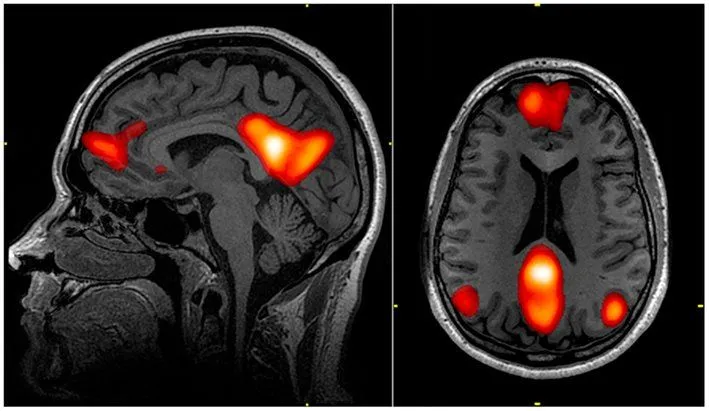

However, one thing that is common in all cases is that, although day-dreaming can potentially occur under any circumstance, it’s more likely to happen when a subject feels a slight, temporary disconnection from his primary task. Another hypothesis is that spacing out activates the Default Mode Network, a network of interacting brain regions that are mostly distinct from other areas of the brain, but are highly correlated to each other.

This part of the brain is activated when someone is at “wakeful rest”, i.e. not focused on what’s going on around them. The DMN is frequently activated when one thinks about their past or future, or when they are having a particularly introspective moment!

Part of why the default mode network has that name is because it activates by ‘default’ when an individual is not strongly involved in a given task. As you might have guessed, the DMN is negatively correlated with the attention networks of the brain. So, just because a person appears super-attentive doesn’t mean they’re actually paying attention.